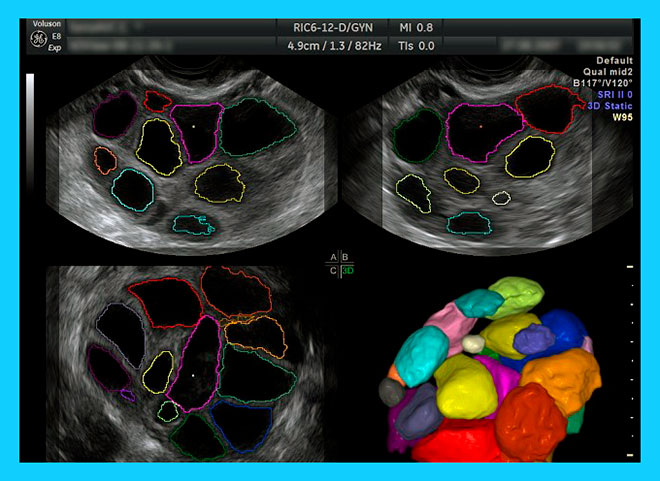

Продолжительность терапии зависит от картины уровня эстрогенов. Обычно к 3-5 дню нового цикла уровень эстрогенов снижается до необходимого. Тогда назначается параллельная ХГЧ-стимуляция. Весь этап стимуляции проходит под УЗИ-контролем. Это необходимо, чтобы не пропустить момент, когда доминантный фолликул приобретет размер 18-19 мм. Тогда диферелиновые инъекции прекращаются, через сутки отменяется и ХГЧ-стимуляция, производится пункция яичника.